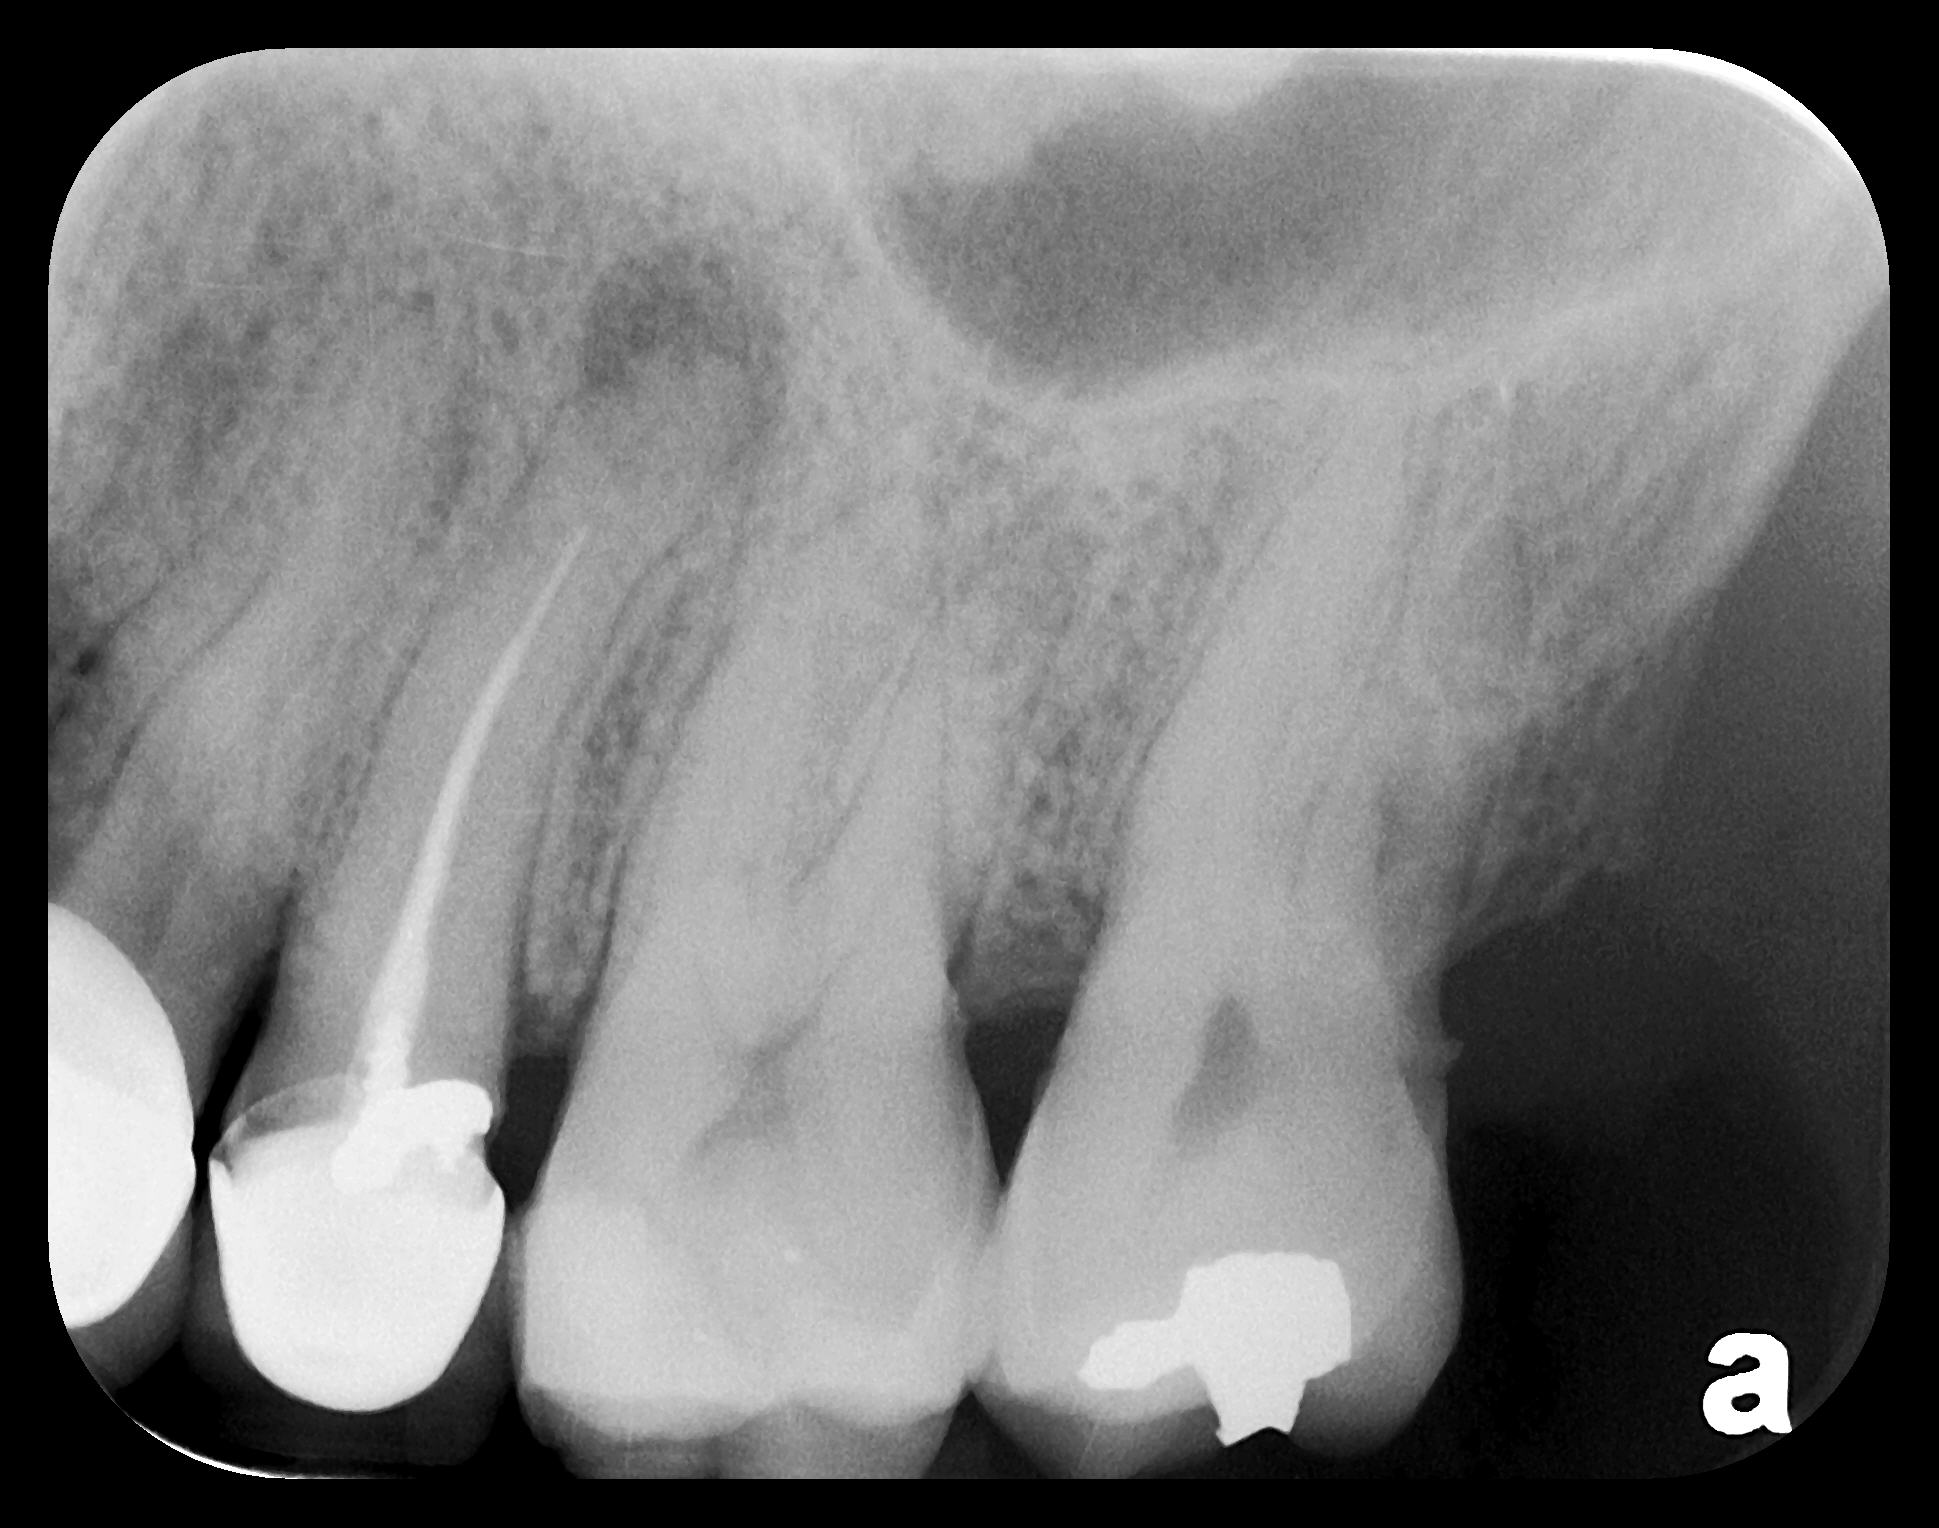

Fig 3. Two PSP PA radiographs of mandibular teeth showing: left, the initial view

of molar area and suspected pathology surrounding impacted tooth No. 32; center,

subsequently exposed PA radiograph, placed more distally, demonstrates extent

of large cyst as well as entire tooth and root No. 32. Proper alert as to presence

of suspected cyst and appropriate referral for 3D CBCT study and surgical

enucleation was given to the patient. Right: Same radiograph as on the left, but

with lighter superimposed outline of the area that would be visible using an HW

sensor rather than a PSP sensor. The small area of pathology is likely obscured

because it is visually overlaid by the root of tooth No. 31. Neglect of this significant

pathology may have resulted.

Figure 3